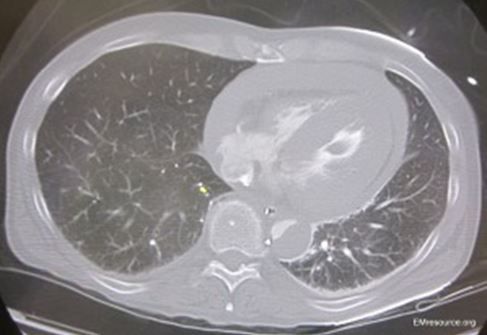

CT examination of chest